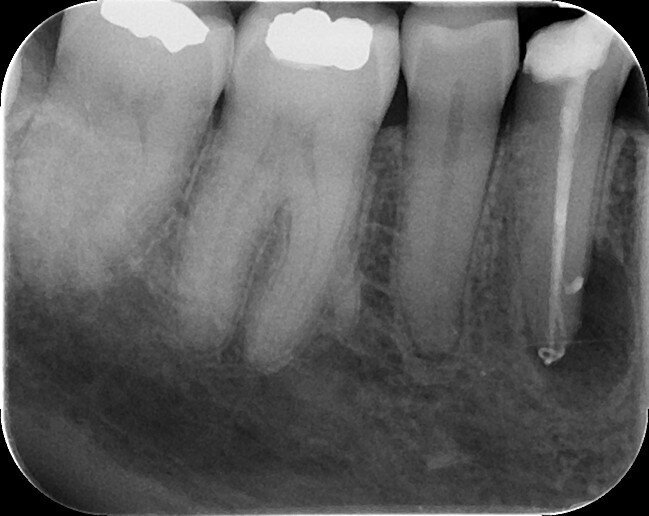

A 63-year-old female patient was referred to my UK practice for root canal therapy of tooth #44. The tooth did not respond to the cold sensitivity test and was slightly tender on percussion. The patient complained of previous episodes of swelling of the buccal gingiva. From analysis of the periodical radiograph, a wide occlusodistal cavity and a J shaped radiolucency in the apical area of this tooth were noticeable (Fig. 1). The root canal was visible until 8 or 9 mm from the apex and then disappeared. This kind of disappearance is often present in teeth with a Type V anatomy, where one root canal leaves the pulp chamber and divides shortly before the apex into two separate and distinct root canals with separate apical foramina (Vertucci classification[3]). This kind of root canal was very difficult to shape with the first generations of nickeltitanium files and required extensive removal of sound dental tissue in order to gain straight access to the canals.

Fig. 1